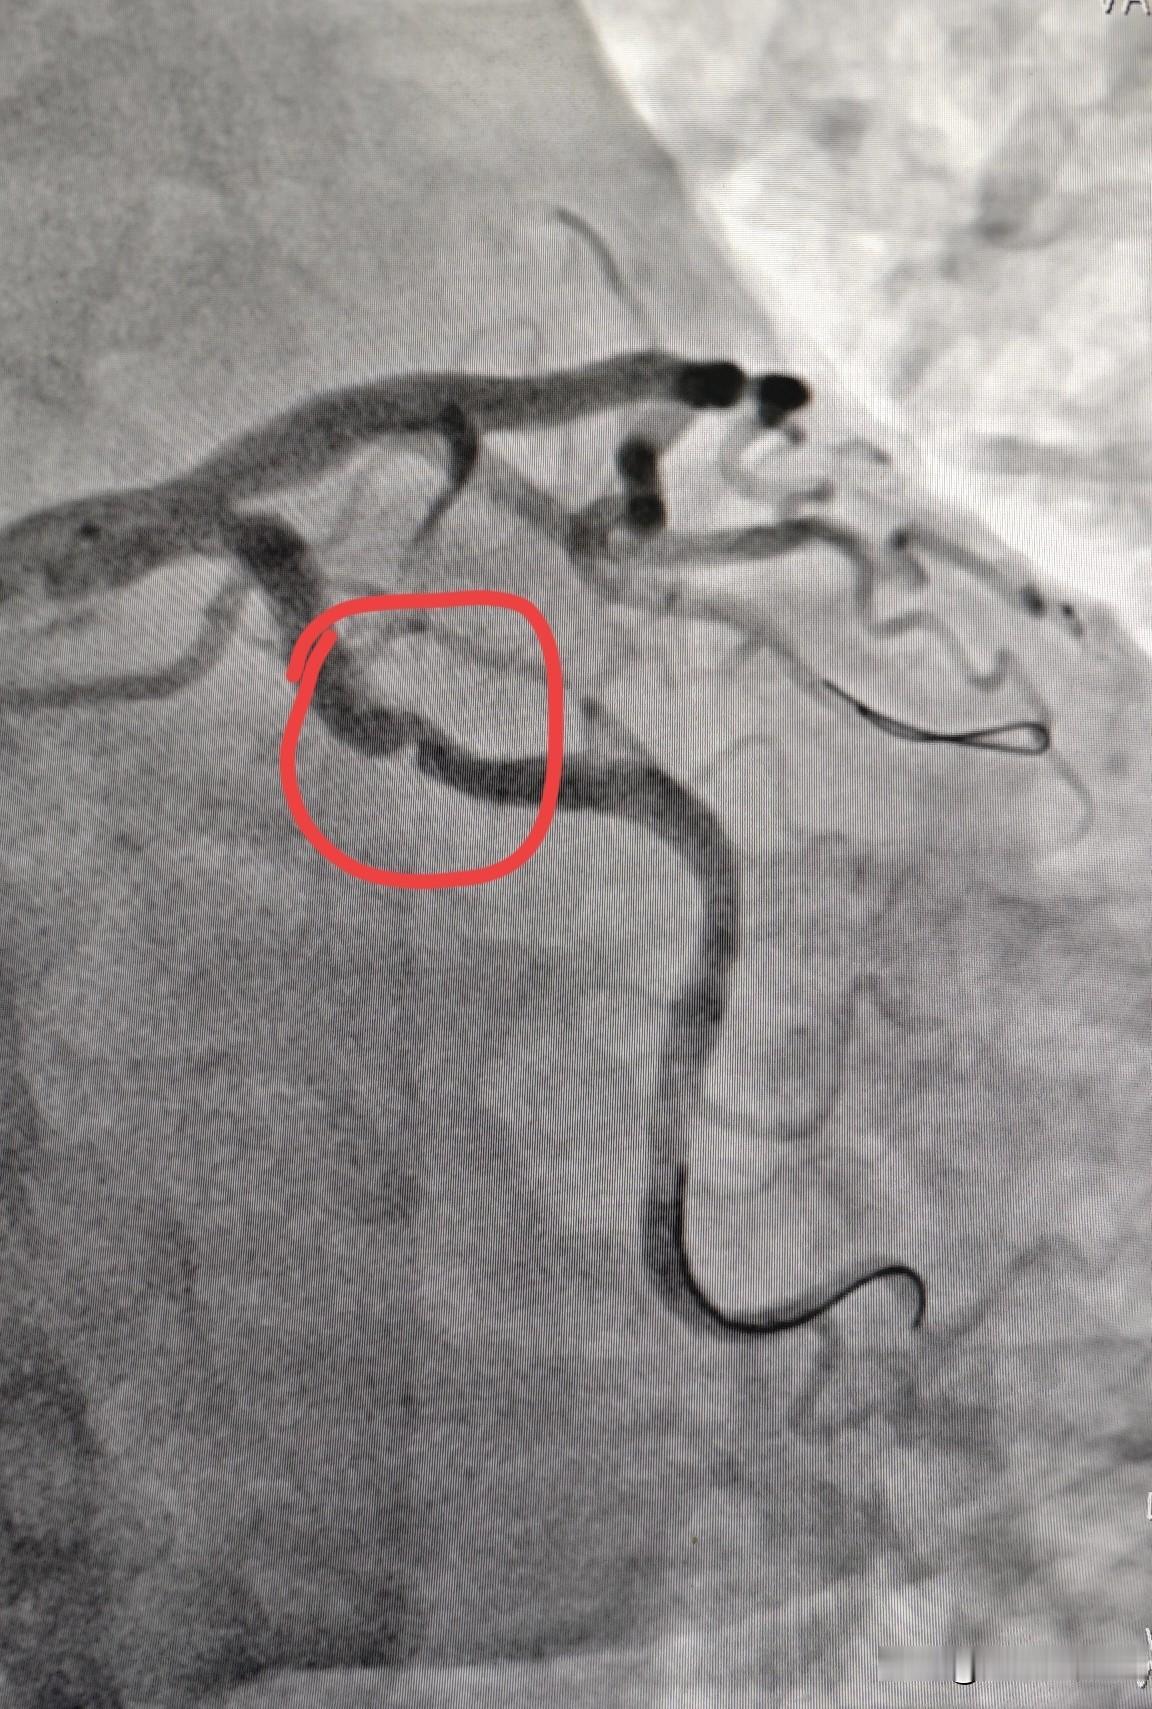

冠状动脉痉挛什么样?快来直观看一下冠状动脉痉挛。 这是一个做冠脉支架的患者,在导丝通过回旋支时,原本没有病变的回旋支出现了一个充盈缺损,类似于动脉斑块的表现(图1)。在冠脉内注射硝酸甘油以后,再次造影,发现充盈缺损消失,狭窄解除(图2)。 这就是在导丝的刺激下,原本没有病变的血管因为痉挛收缩了,从而形成一个血管狭窄的假象。但这种狭窄在使用硝酸甘油等扩血管药物后就会解除。 临床上有一种心绞痛,就叫变异性心绞痛,就是冠状动脉痉挛引起的。这种冠状动脉痉挛一般在使用硝酸异山梨酯或者是盐酸地尔硫卓以后,冠状动脉痉挛就可以得到控制,心绞痛的症状就可以得到缓解。冠心病 冠动脉狭窄